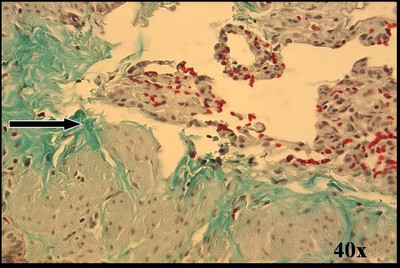

Rat lung trichrome